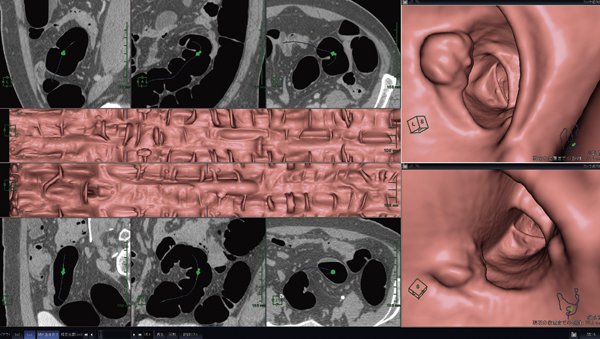

まず,最適な読影インターフェイスについて述べる。大腸解析ソフトウェアには,腸管の経路を追跡し,その経路に沿って仮想内視鏡モードを走行させ,大腸の内壁の構造物を観察しやすく表示する目的がある。診断は,原画像をもとになされるが,検出という意味では,仮想内視鏡モードで突起物などを認識した方がストレスは少ない。当社のソフトウェアは,そのような状態を顧みて構築されている。ビューアには,仮想内視鏡モードと,仮想内視鏡の視点と同じ方向のMPRを対にして表示している。これにより,(1) 仮想内視鏡による突起物の検出,(2) 突起物をビューア上でクリック,(3)突起物を軸に,MPRで形状とCT値の確認を容易に行うことができる。前述の肝臓解析ソフトウェアは,目的が治療補助であったが,大腸解析ソフトウェアは,このように読影補助を目的に設計されていることから,三次元画像とMPRが常に連動する仕組みを持っている。また,別体位の比較モードや大腸の展開表示,エアー像の表示も備えており,さまざまな読影方法に対してもアプローチが可能になるよう開発されている(図4)。

図4 大腸解析レイアウト